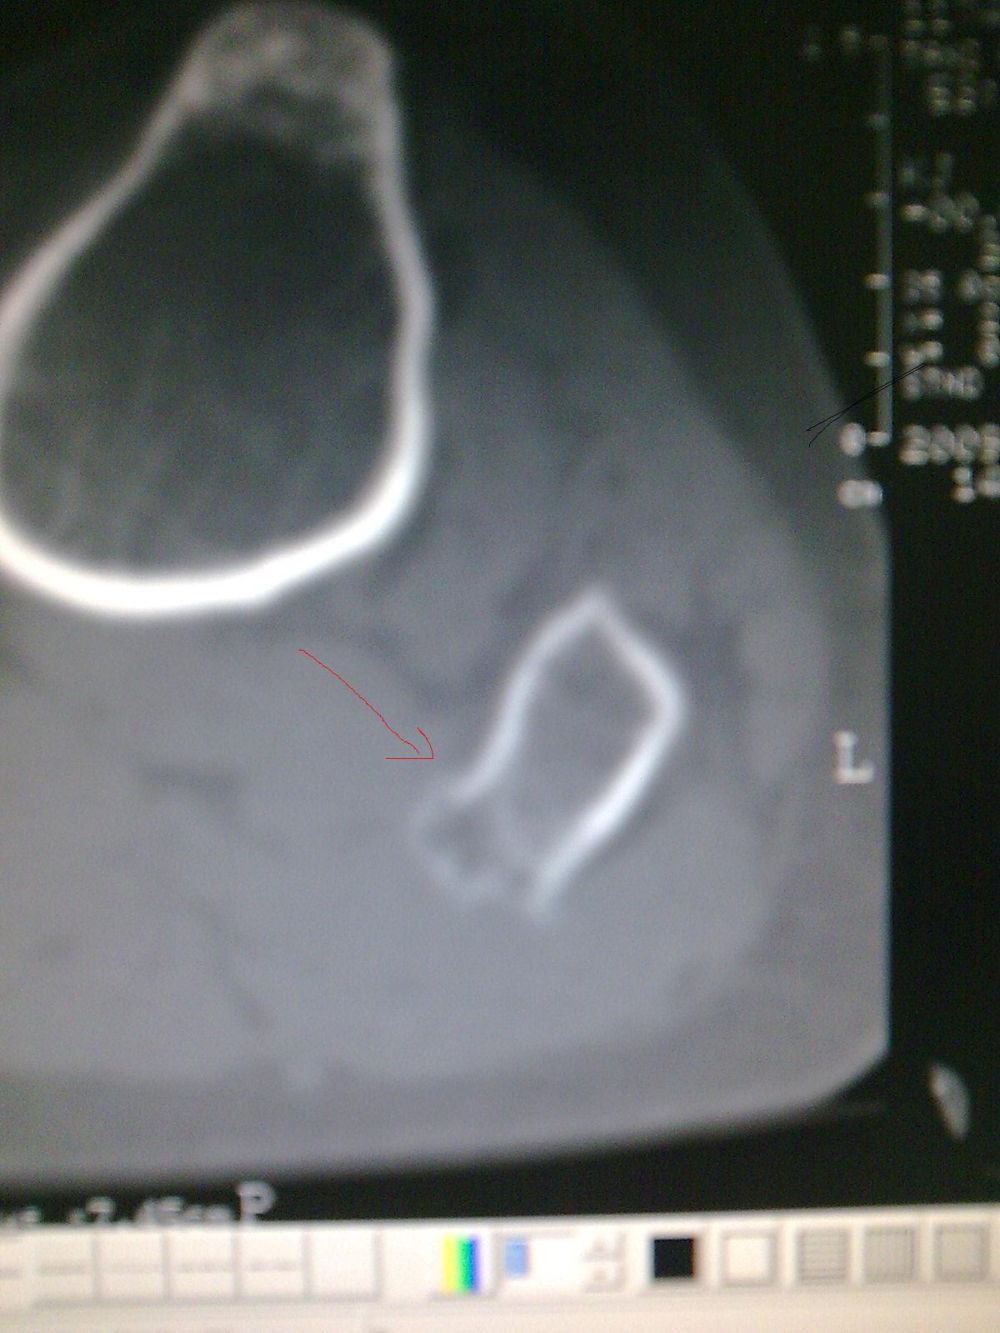

标题: CT19437:男性,四十岁,因外伤入院,X光平片发现腓骨近端 [打印本页]

标题: CT19437:男性,四十岁,因外伤入院,X光平片发现腓骨近端

建议除外骨肿瘤【典型骨肉瘤ct表现。1局部骨破坏,2骨膜反应,3周围软组织肿块;4,与骨膜肉瘤难区别】

kaolv 骨软骨瘤

考虑腓骨上端骨软骨瘤。

首先考虑比目鱼肌牵曳征,其次考虑骨软骨瘤。